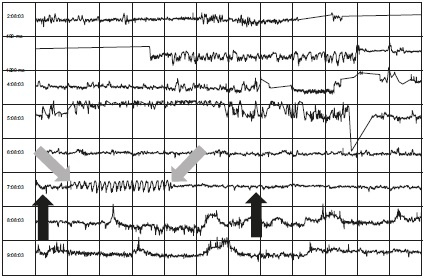

Рисунки 7.5A и 7.5B демонстрируют два примера людей с очень слабой вариабельностью сердечного ритма, отмеченной стрелками под буквой A в естественном бодрствующем состоянии. Взгляните на изменения в вариабельности сердечного ритма, когда они практикуют сердечную когерентность, отмеченную стрелками под буквой B. Даже если это длится всего от 5 до 10 минут, они изменяют свою биологию.

Иллюстрация к книге — Сверхъестественный разум. Как обычные люди делают невозможное с помощью силы подсознания [i_046.jpg]

Рисунок 7.5A